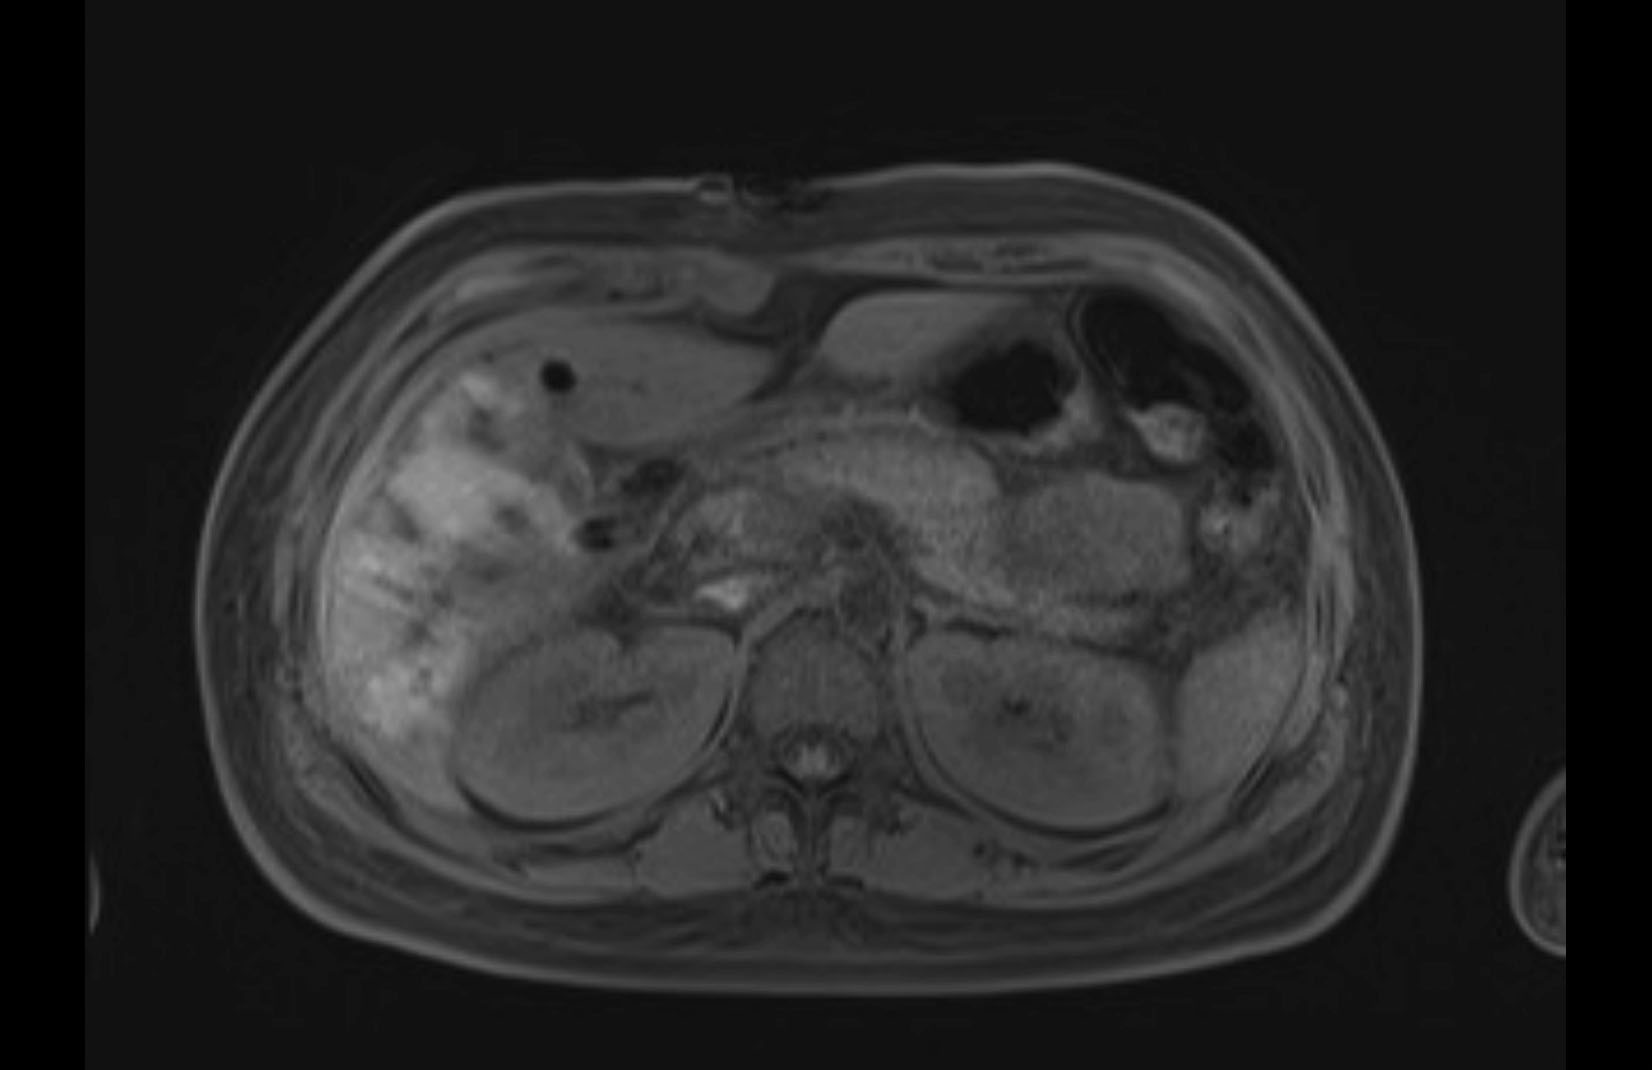

MRI T1

MRI T2